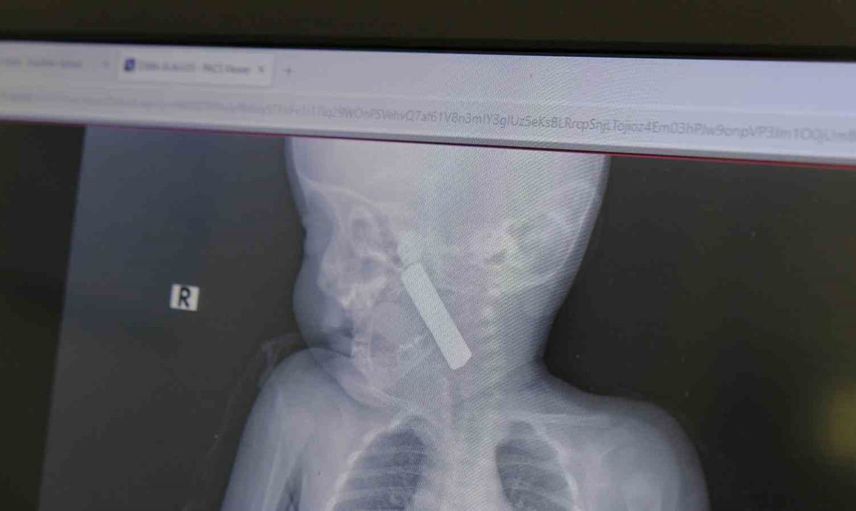

Karaman Eğitim ve Araştırma Hastanesi acil servisine kusma şikayetiyle getirilen 6 aylık E.A. isimli kız bebeğin yapılan muayene ve tetkiklerinde boğazına kumanda pili kaçtığı tespit edildi. Solunum güçlüğü yaşayan bebek, çocuk cerrahisi ekibi tarafından acilen ameliyata alındı.

Yapılan tetkiklerde pilin ağız tabanına oturduğu ve yemek borusunun birinci darlığına kadar uzandığı görüldü. İlk muayenede bebekte belirgin siyanoz ve solunum sıkıntısı vardı; oksijen satürasyonunun yaklaşık 90 civarında olduğu bildirildi. Durum acil olduğundan, ekip vakit kaybetmeden ameliyathaneye yöneldi.